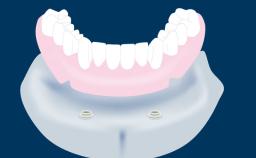

Fixed and removable prosthodontic implant therapy for restoration of the edentulous maxilla is both complex and challenging. Careful assessment and planning is needed in each individual case to explore whether a fixed or a removable solution will be the more suitable to satisfy the patient’s preference for optimal esthetics, phonetics, comfort and function. This Learning Pathway explores the prosthodontically driven treatment planning based on structured assessment, considered diagnosis and practical application in clinical case examples.

• recognize the importance of a prosthodontically driven plan and of planning implant configurations and placement accordingly

Edentulous Maxilla Fixed vs. Removable Prosthodontics Planning Principles Prosthodontic Planning & Procedures Prosthodontic Planning & Procedures